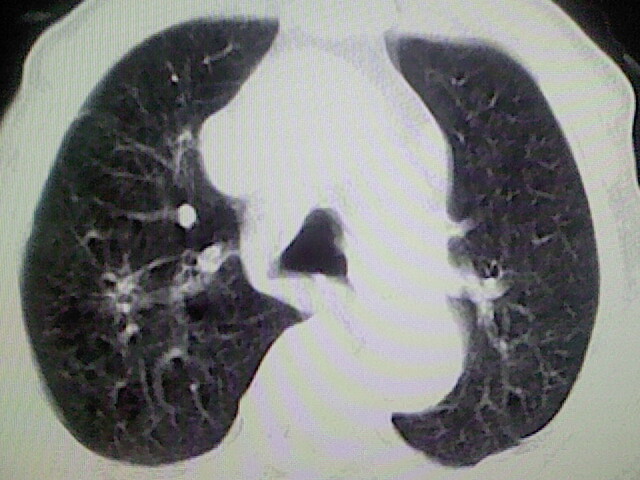

以下是引用zsl6918在2008-8-28 16:49:00的发言:[br]双肺炎性病灶,食管狭窄估计与心房增大压迫所致。

以下是引用xulianj在2008-8-28 20:36:00的发言:[br]慢支肺气肿伴感染,右上肺陈旧性结核;食道建议胃镜检查。

以下是引用wqs571018在2008-8-28 21:18:00的发言:[br]慢支继发感染,右上肺陈旧性结核;食道建议胃镜检查。